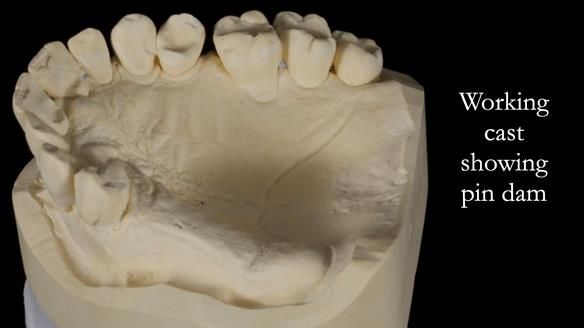

Welcome to Newsletter 64. I'll walk you through the process of providing a Mk 2 metal-based partial denture (RPD), for Ian a retired Veterinary Surgeon aged 78. The RPD was made at an increased vertical dimension and acted as an occlusal stabilisation splint - reducing the wear and bite force on the remaining natural teeth.